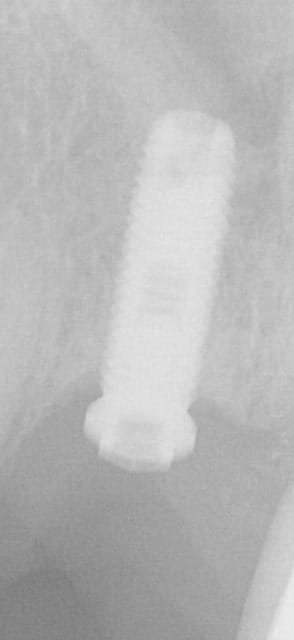

Auriez vous une idée sur le type d'implant?

La vis prothétique s'est fracturée...

Nobel MK3...;-)

la vis est vraisemblablement en or...pas forcément le plus simple à retirer car l'or se matte sur le filetage en titane...